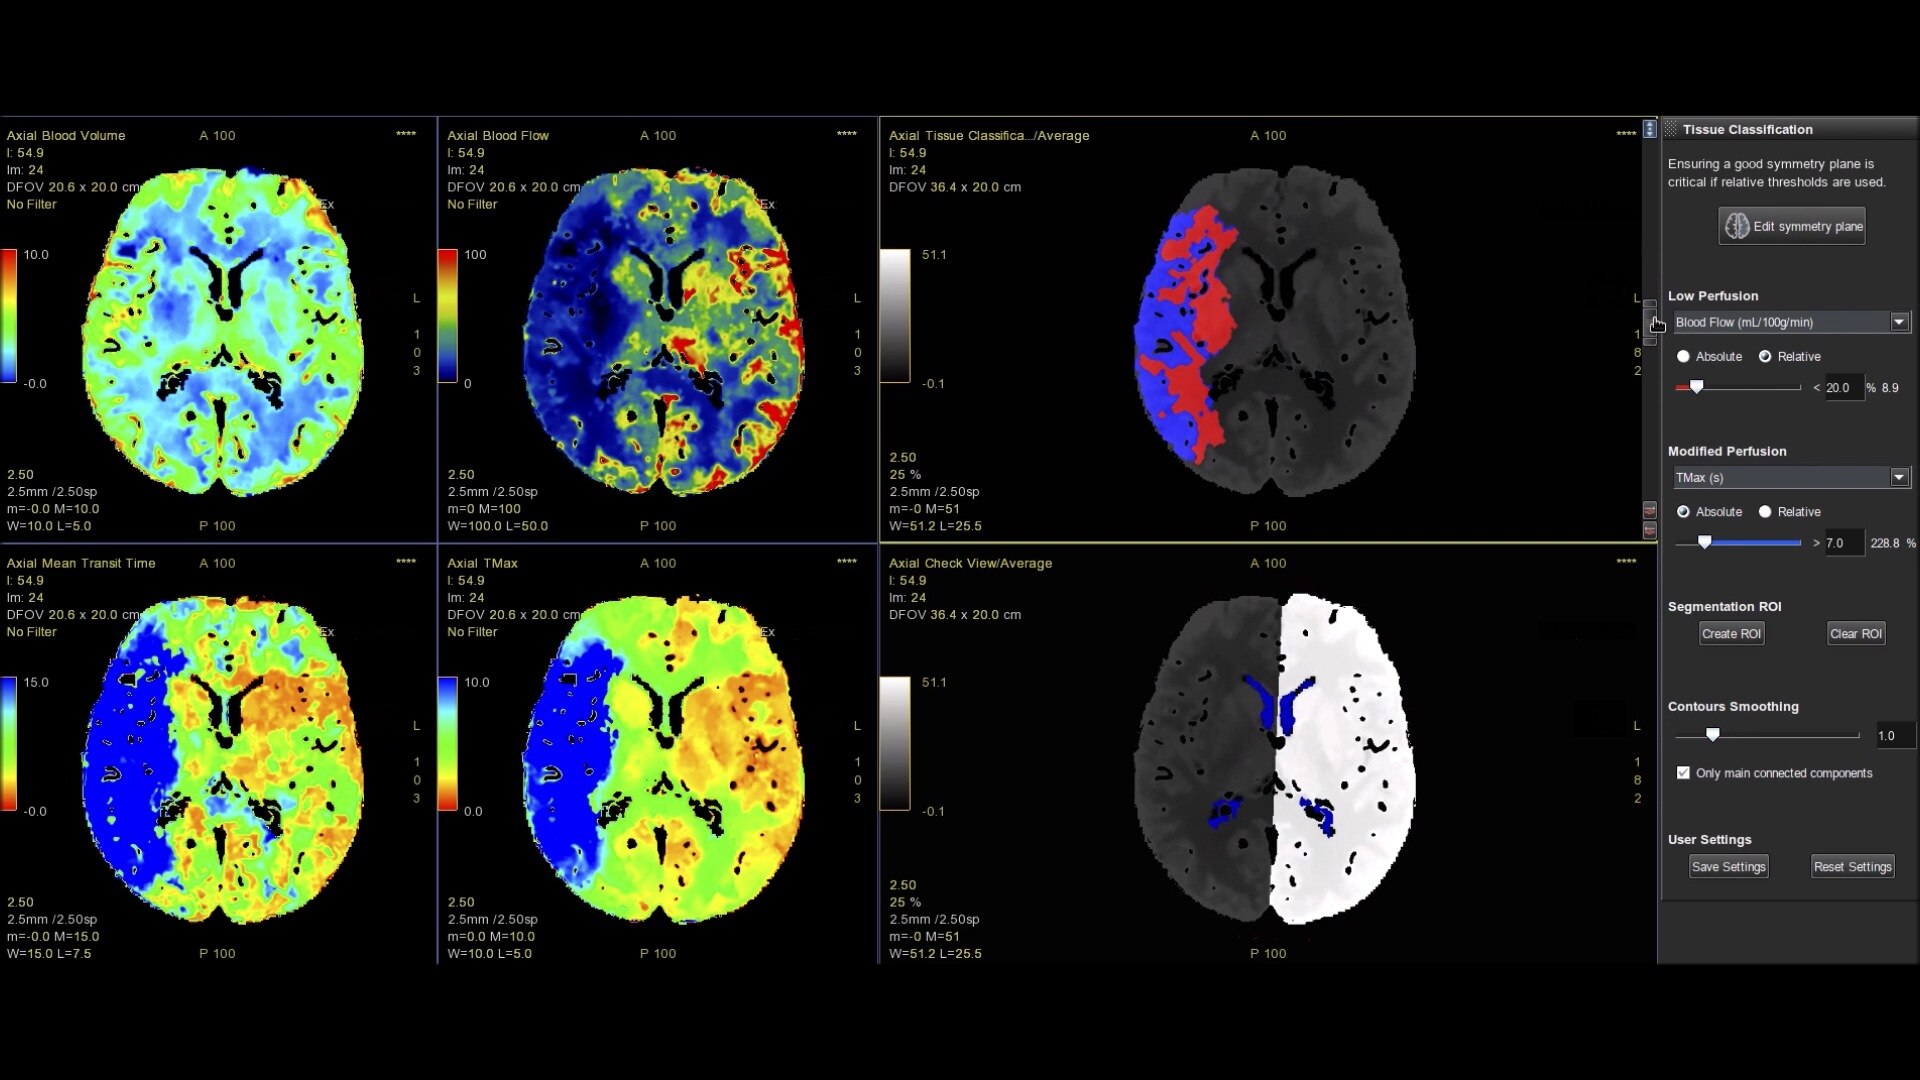

• Tissue Classification map segmented from absolute or relative values, customizable thresholds and user selectable input maps

• Mismatch volume and ratio calculated from the Modified Perfusion region and the Low Perfusion region

4-perfusion-maps-desktop